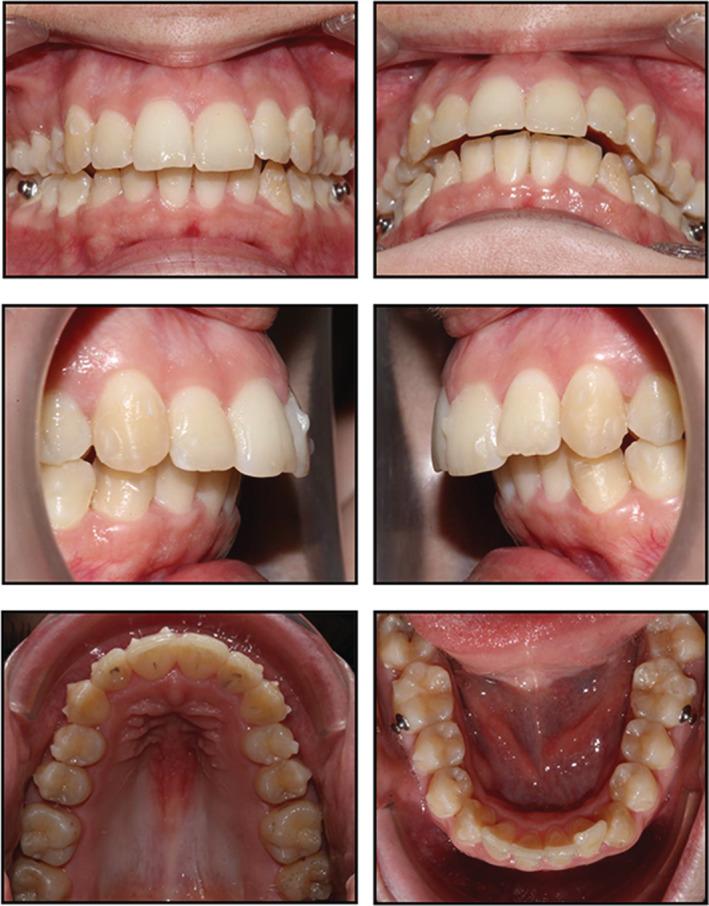

To describe an esthetic orthodontic treatment using aligners in an adult patient with dental class II malocclusion associated with crowding. A 25-year-old female patient with skeletal class I, bilateral class II relation, increased overjet and overbite and crowding in both arches presented for orthodontic treatment. The patient refused conventional fixed multibracket treatment in favor of aligners. Pre- and post-treatment records are presented. Treatment objectives were achieved in 10 months, and the patient was satisfied with the functional and esthetic outcomes. Combining aligners with appropriate attachment location and geometry is an efficacious means of resolving orthodontic issues such as class II malocclusion in a time frame comparable to that of conventional fixed orthodontics. Staging in distalization increases the predictability of movement. Furthermore, this system is associated with optimal oral hygiene and excellent esthetics.

描述在一名患有伴有牙列拥挤的安氏II类错牙合的成年患者中使用隐形矫治器进行的美学正畸治疗。一名25岁女性患者,骨骼I类,双侧安氏II类关系,覆盖和覆牙合增加,上下牙弓均有拥挤,前来接受正畸治疗。患者拒绝传统的固定多托槽治疗而选择隐形矫治器。展示了治疗前和治疗后的记录。在10个月内实现了治疗目标,患者对功能和美学效果感到满意。将隐形矫治器与合适的附件位置和几何形状相结合,是在与传统固定正畸相当的时间范围内解决诸如安氏II类错牙合等正畸问题的有效方法。远中移动分阶段进行可提高移动的可预测性。此外,该系统有助于保持最佳的口腔卫生并具有出色的美学效果。